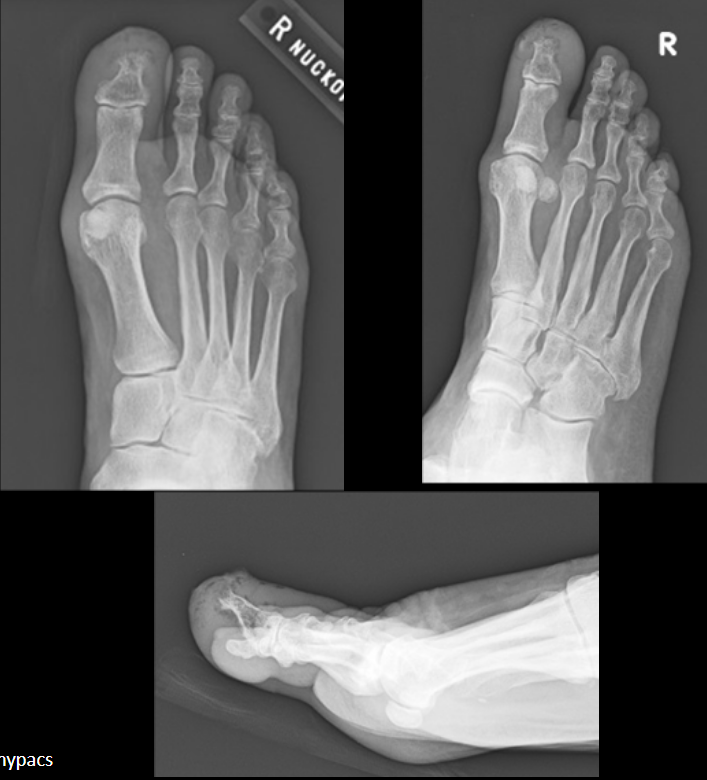

Patient is radiographed 10 days after onset of forefoot pain.

Which structure is affected by avascular necrosis?

A

Third metatarsal head

Freiberg disease

16

Q

Patient is radiographed 19 days after onset of forefoot pain.

What is the diagnosis?

What are two underlying conditions which may result in this specific diagnosis?

Diabetes, alcoholism

osteochondrosis (AVN) of metatarsal head (3rd)